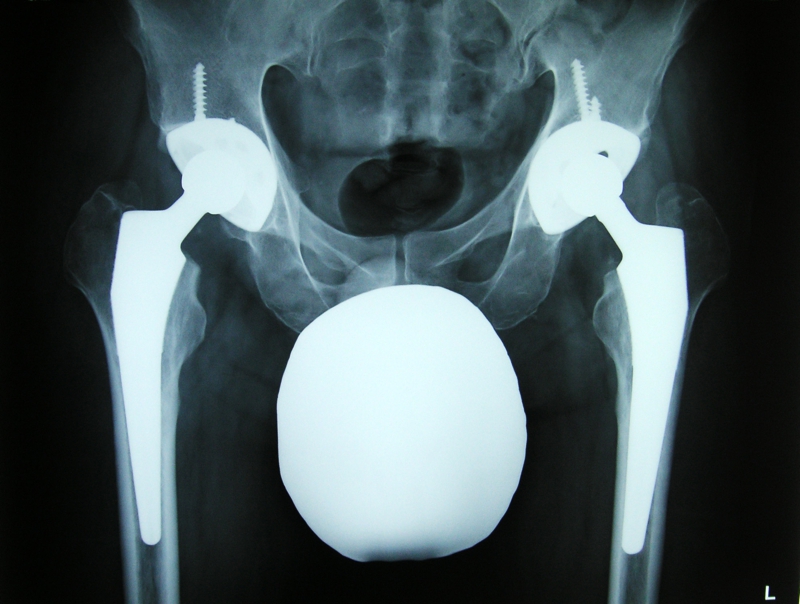

| 2008/03/26 地元の公園 | 2008/02/21 サイボーグ・最終形体 | 2008/02/03 備え付けのTVより便利でした。 | 2007/11/10 脱臼防止だが、静止芸は辛いです。 | 2007/08/26 スティーリー・ダンが生で見られるなんて!! |